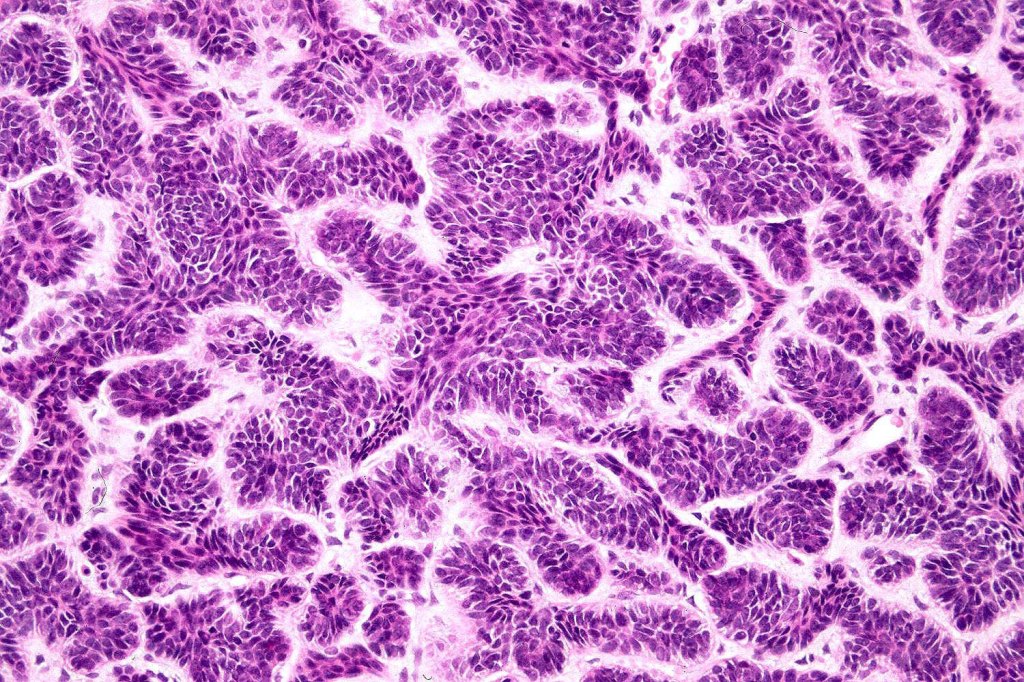

•The classical appearance consists of keratocysts & lobules of basaloid cells

•Basaloid lobules show peripheral palisading

•Retraction artifact and mucin deposition as seen in BCC are not present

•Perifollicular mesenchyme is always conspicuous and sometimes densely aggregated are seen indenting the baslaloid lobules (papillary mesenchymal bodies)

•Narrow epithelial strands arising from the basaloid lobules are often present

Trichoepithelioma should be distinguished from trichoblastoma since the latter is very rarely syndromic. Trichoepithelioma is largely a dermal tumor whereas trichoblastoma often extends from the dermis into subcutaneous fat or deeper in very large examples. Papillary mesenchymal bodies are much better formed and generally more obvious in trichoepithelioma. Trichoepithelioma must also be distinguished from basal cell carcinoma. Retraction artifact & stromal mucin are features of basal cell carcinoma and not trichoepithelioma. Papillary mesenchymal bodies are not seen in basal cell carcinoma.